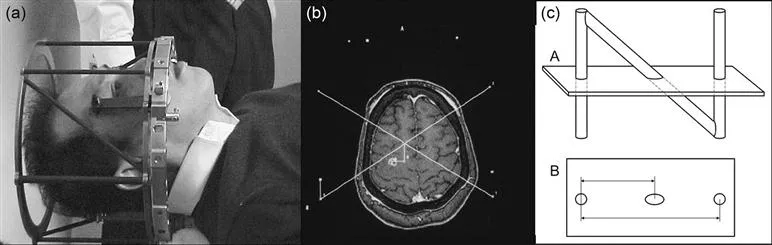

The availability of three-dimensional data was not lost on the stereotactic community but there was a lack of clarity as to how to make use of it. This was addressed when Russell Brown14 developed the simple but elegant N-localizer system. This system is shown in Figure 1.2.

Because the X and Y location of any target could be visualized and the height above the base ring calculated, each image held the target coordinates. By having two lateral and one AP sets of N-bars, the orientation of the image plane could also be determined from any tomographic image in which the N-bars were visible.

It did not take the innovators in stereotactic surgery long to embrace the new technology. Leksell15 and Mundinger16 both published papers on using the new technology. Gildenberg17 even developed a technique for creating quasi-AP and Lateral images from CT so that surgeons with old calculation methods could use the images. But it was two surgeons with access to greater computational intensity who began to see the real value. By using the N-bars they could confirm the orientation and spacing of the CT slices. That allowed them to trust the volumetric nature of the scan and to use it not merely for neuroelectrical interventions but for volumetric resections. This work was led by Shelden18,19 and Kelly...